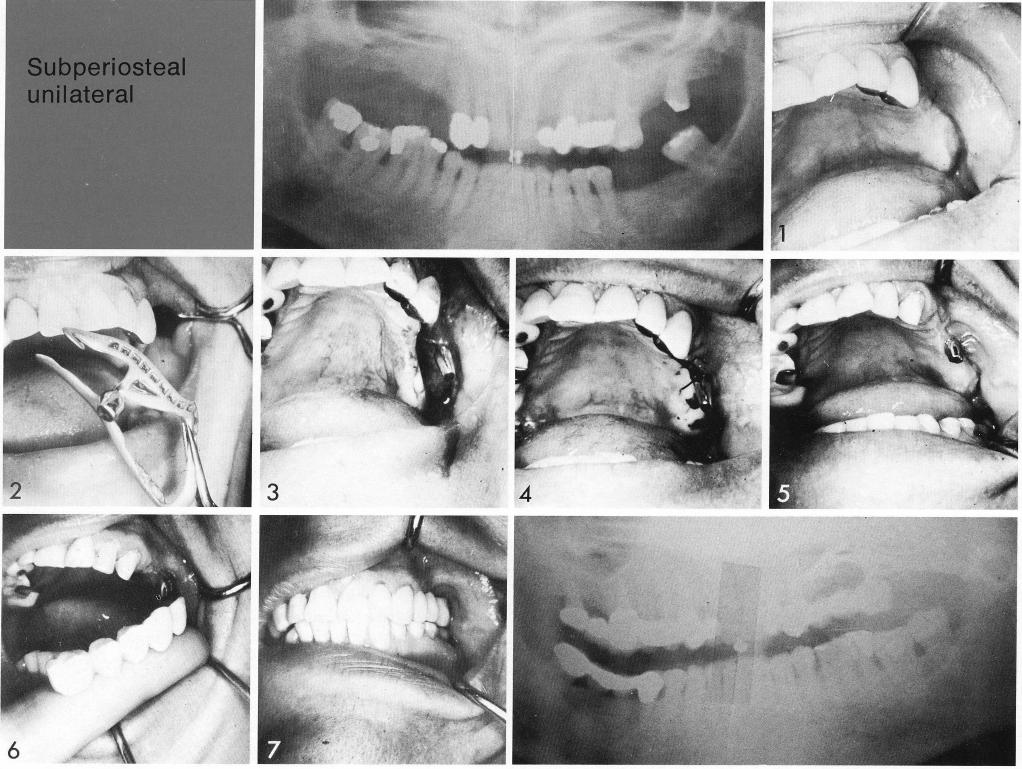

In another unilateral case (1), a subperiosteal implant (2) was used as posterior anchorage (3,4). An impression was taken of the healed tissues (5), and a five-unit splint fabricated (6) and affixed (7).

1 The maxillary subperiosteal implant used as a posterior anchorage